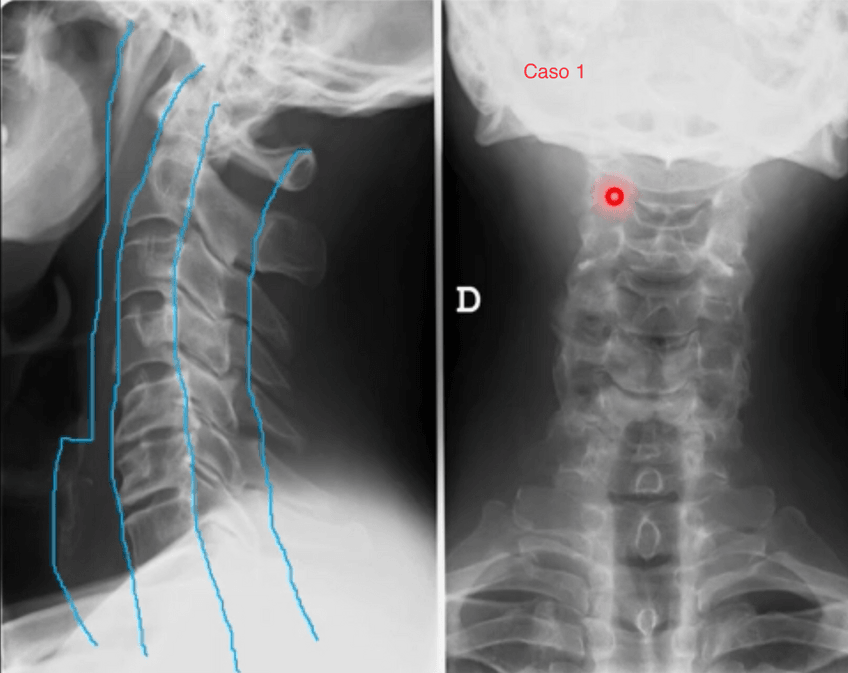

practicas-de-columna-vertebral.pdf